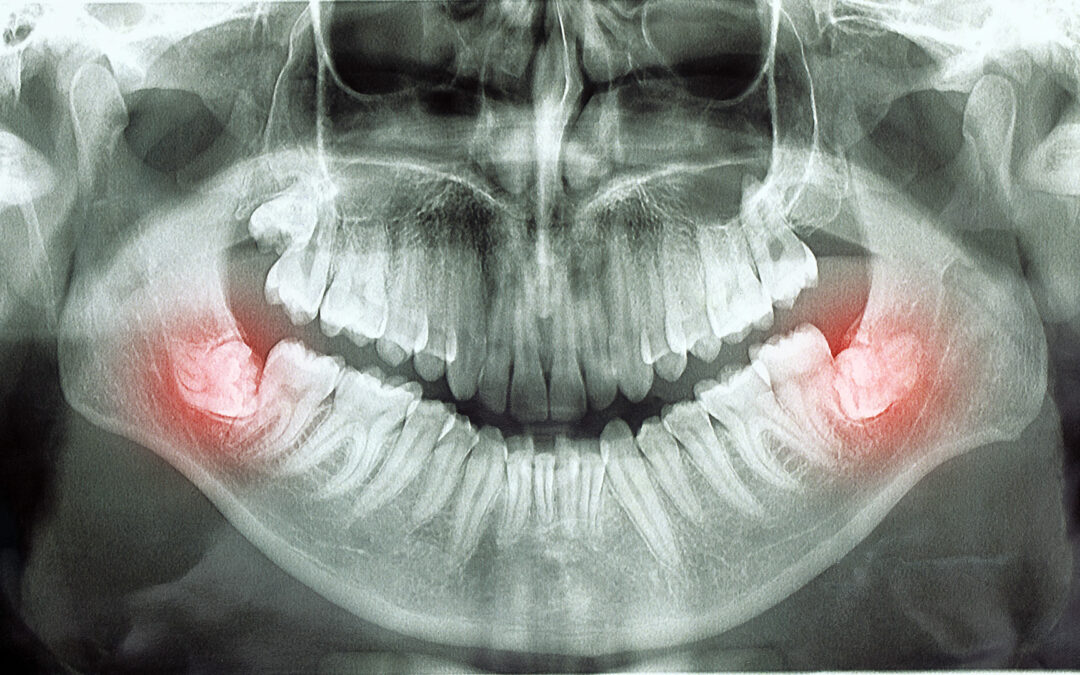

The procedure for wisdom teeth removal involves a thorough examination, possibly including X-rays, to determine the best approach. Typically performed in an outpatient setting, the surgery allows you to return home the same day. Various anesthesia options are available, from local anesthesia to sedation methods, ensuring comfort during the procedure. The process of having teeth surgically removed usually lasts about 45 minutes to an hour, depending on complexity. You’ll receive detailed post-operative care instructions for a smooth recovery after wisdom extraction.